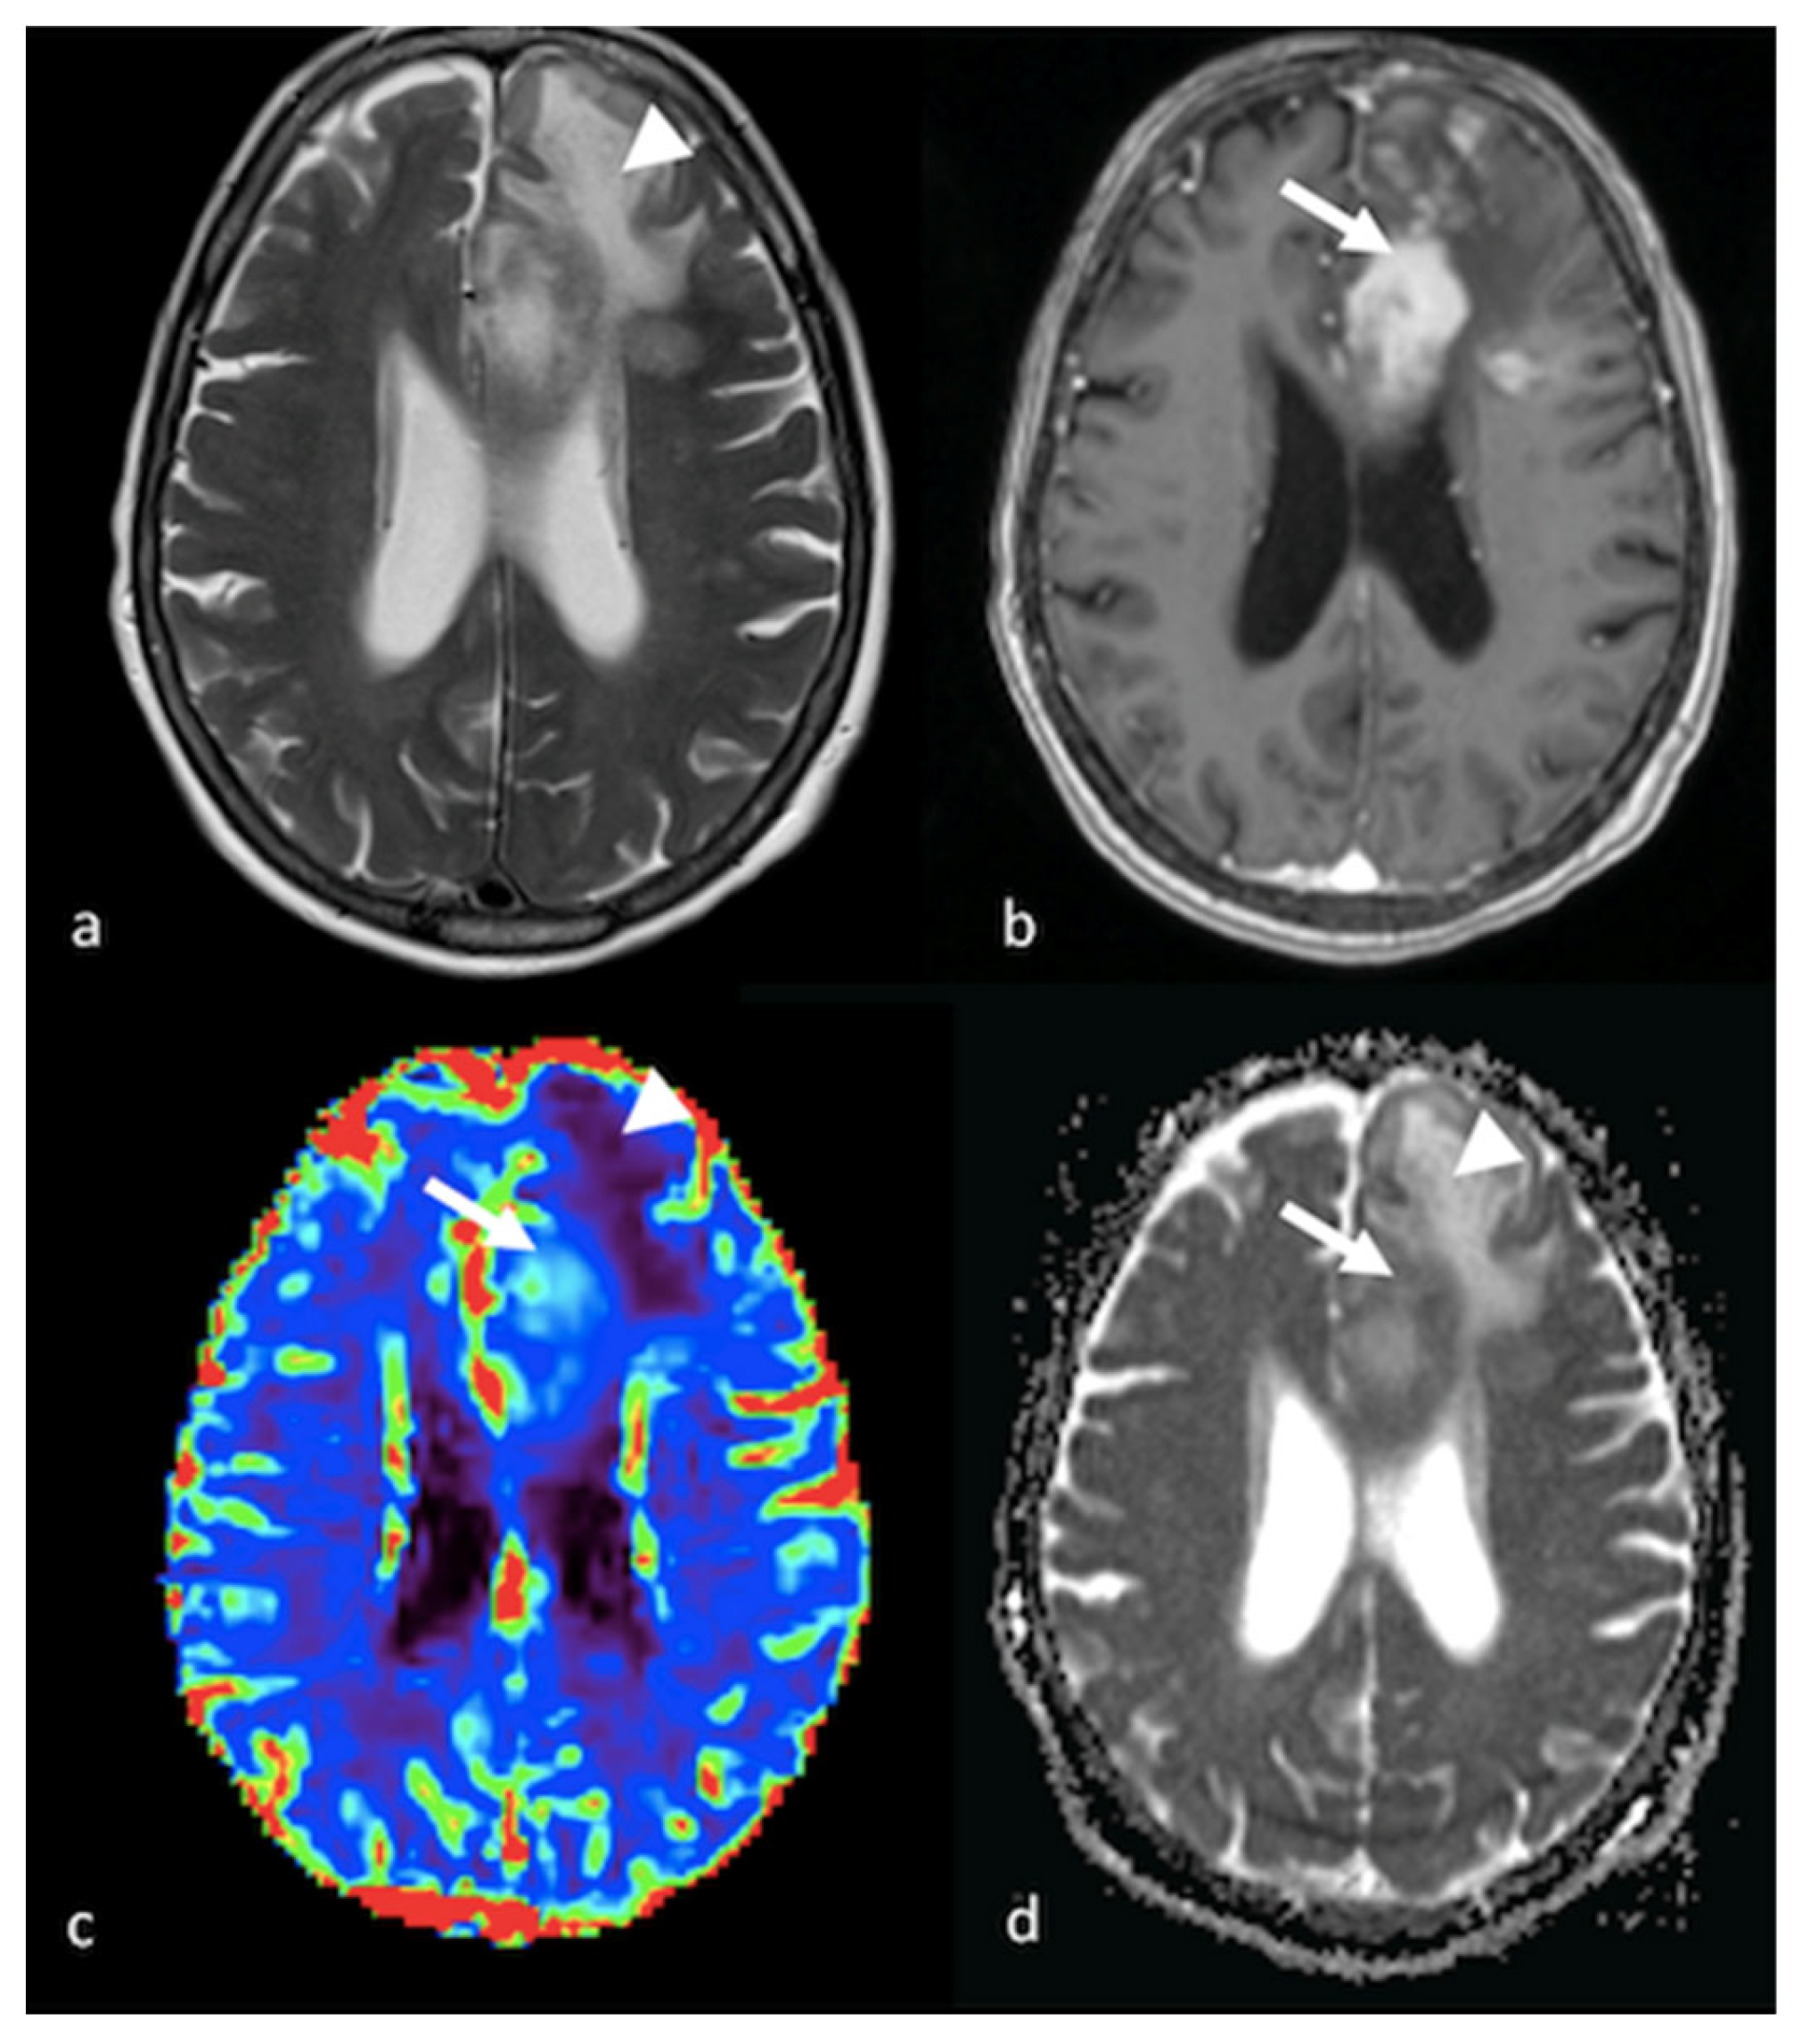

3.2. Diffusion Imaging Techniques

3.2.1. Diffusion-Weighted Imaging (DWI)

3.3.1. Dynamic Susceptibility Contrast-Enhanced Perfusion

- Halshtok Neiman, O.; Sadetzki, S.; Chetrit, A.; Raskin, S.; Yaniv, G.; Hoffmann, C. Perfusion-weighted imaging of peritumoral edema can aid in the differential diagnosis of glioblastoma mulltiforme versus brain metastasis. Isr. Med. Assoc. J. 2013, 15, 103–105. [Google Scholar] [PubMed]

- Neska-Matuszewska, M.; Bladowska, J.; Sasiadek, M.; Zimny, A. Differentiation of glioblastoma multiforme, metastases and primary central nervous system lymphomas using multiparametric perfusion and diffusion MR imaging of a tumor core and a peritumoral zone-Searching for a practical approach. PLoS ONE 2018, 13, e0191341. [Google Scholar] [CrossRef]

- Lin, L.; Xue, Y.; Duan, Q.; Sun, B.; Lin, H.; Huang, X.; Chen, X. The role of cerebral blood flow gradient in peritumoral edema for differentiation of glioblastomas from solitary metastatic lesions. Oncotarget 2016, 7, 69051–69059. [Google Scholar] [CrossRef] [PubMed]